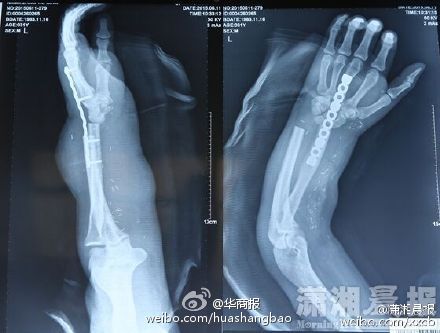

2015年7月17日,一則男子斷手寄養在小腿的新聞在微博引起熱議。把斷掉手臂的手掌寄養的小腿上,并通過手術重新將手移植到男子手上,這個手術被不少網友稱為現實版寄生獸。

在今年5月5日,湘潭周先生在車間操作設備時,其左手前手臂不慎被螺旋葉片絞斷。為了重新讓周先生的手掌重新再生,醫生通過將其斷手移植寄生在其小腿上。等到手掌恢復供血之后,再重新通過移植手術將手掌左前掌。

而在近日,周先生順利的完成了手掌的移植手術,經過一段時間的調養,目前已經可以做輕微屈伸。